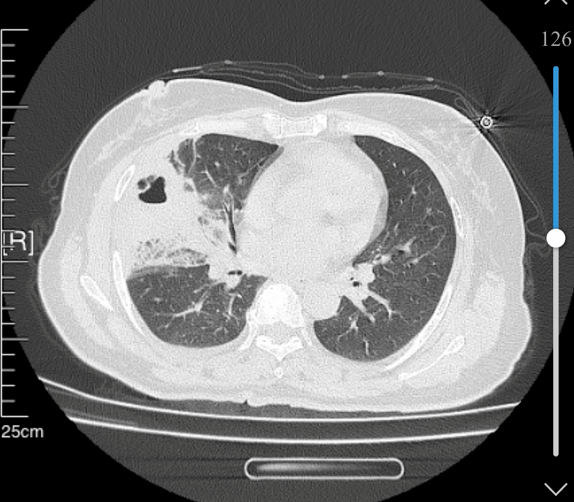

张姨(化名)近期反复出现胸痛不适,伴随轻微咳嗽、乏力,自认为年纪大了心脏易出问题,便在家自行含服救心丸,可症状不仅没有缓解,反而逐渐加重,还出现发热、呼吸不畅等情况。家人急忙将其送至我院,医生详细问诊后,并未盲目排查心脏问题,而是及时安排胸部CT检查,最终明确诊断为右肺中叶脓肿伴严重感染,揪出了“伪装”成心脏病的真凶。

整个操作微创无痛、耗时短、创伤小,术后张姨无明显不适感,当天胸痛、胸闷症状便明显减轻,体温也逐渐恢复正常。经过后续巩固治疗,复查CT显示肺脓肿基本吸收、炎症完全消退,张姨顺利康复出院。